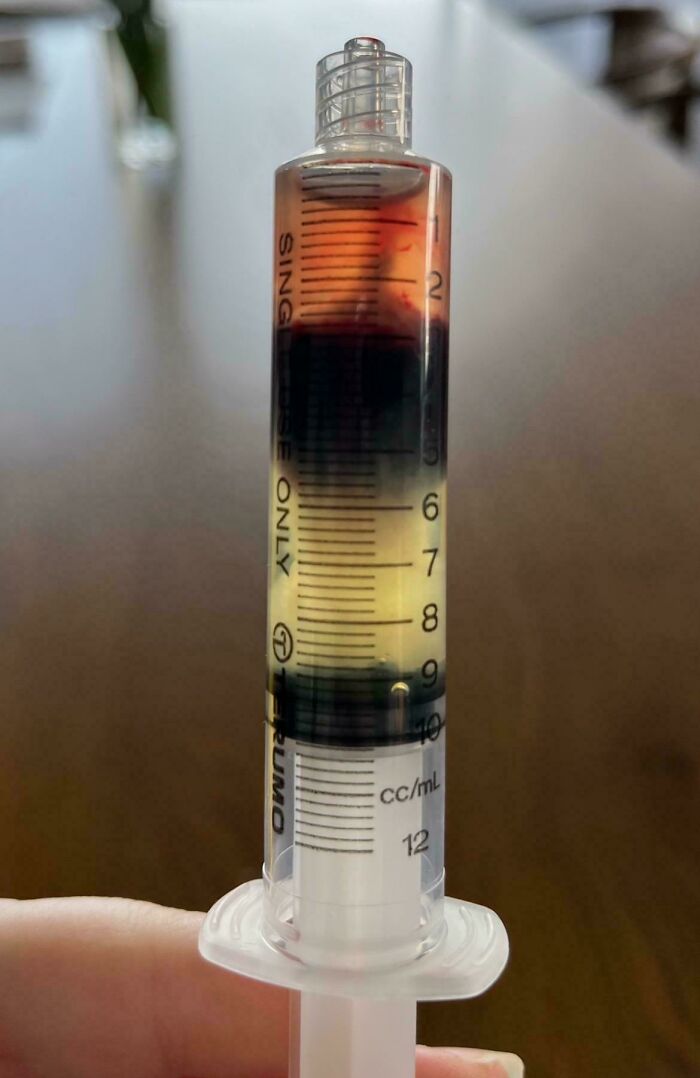

Blood Separates Like a Science Experiment (Around 24 Hours Later)

When blood chills out, it settles into layers - plasma on top, red blood cells at the bottom, and some white cells and platelets in between. It’s just physics doing its thing, making blood look like a layered drink.